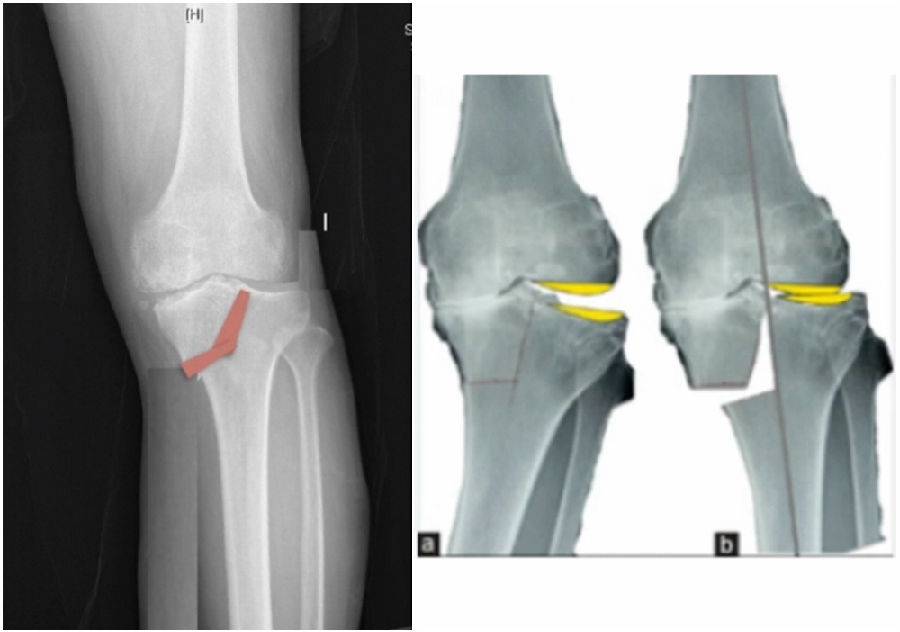

术前规划:

①关节内截骨,内外侧平台平行。

关节内截骨

②再次确定下肢力线。

确定力线

③关节外截骨。

关节外截骨

术中先打克氏针确定截骨方向,先做关节内截骨,截完后测量下肢力线,发现并没达到术前设计的Fujisawa点。

术中影像资料

随后用骨刀继续向前敲,做HTO内侧开放楔,截骨完成后内侧固定,并测量下肢力线,此时达到术前设计的要求。